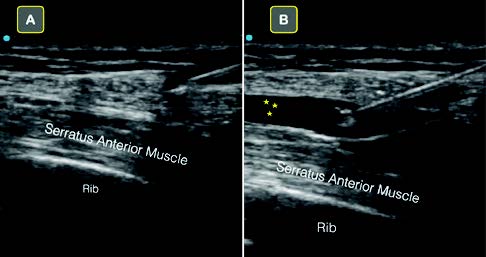

ACEP Now: Vol 40 – No 06 – June 2021Figure 4A: Poorly visualized needle due to low angle of insonation.

Figure 4B: Improved needle visualization after “toeing in” transducer.

Figure 5B: Operator “toes in” transducer.

In our experience teaching ultrasound-guided nerve blocks, locating the needle tip during in-plane blocks is often the most challenging aspect of a procedure. Optimizing ultrasound screen positioning, properly stabilizing the ultrasound transducer with the nondominant hand, “toeing in” the transducer for steep blocks, and using normal saline to both hydrolocate the needle tip as well as hydrodissect fascial planes improve success.